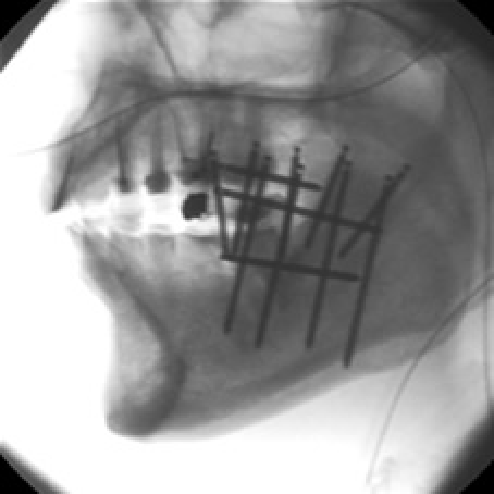

金グレインは直径0.8mm、長さ2.5mmの粒状線源を腫瘍の大きさに応じて、数個から数十個刺入します(線源は刺入したままになります)。

早期の口唇がん、口腔がんに対する密封小線源治療3